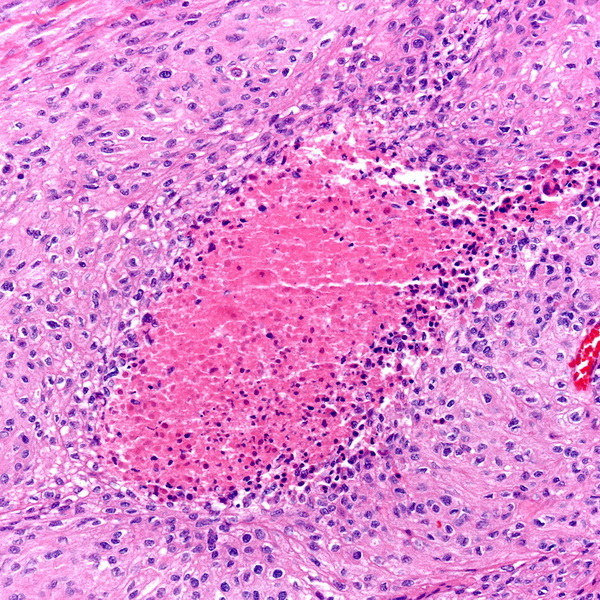

Микрофотографии гистологии глиобластомы головного мозга